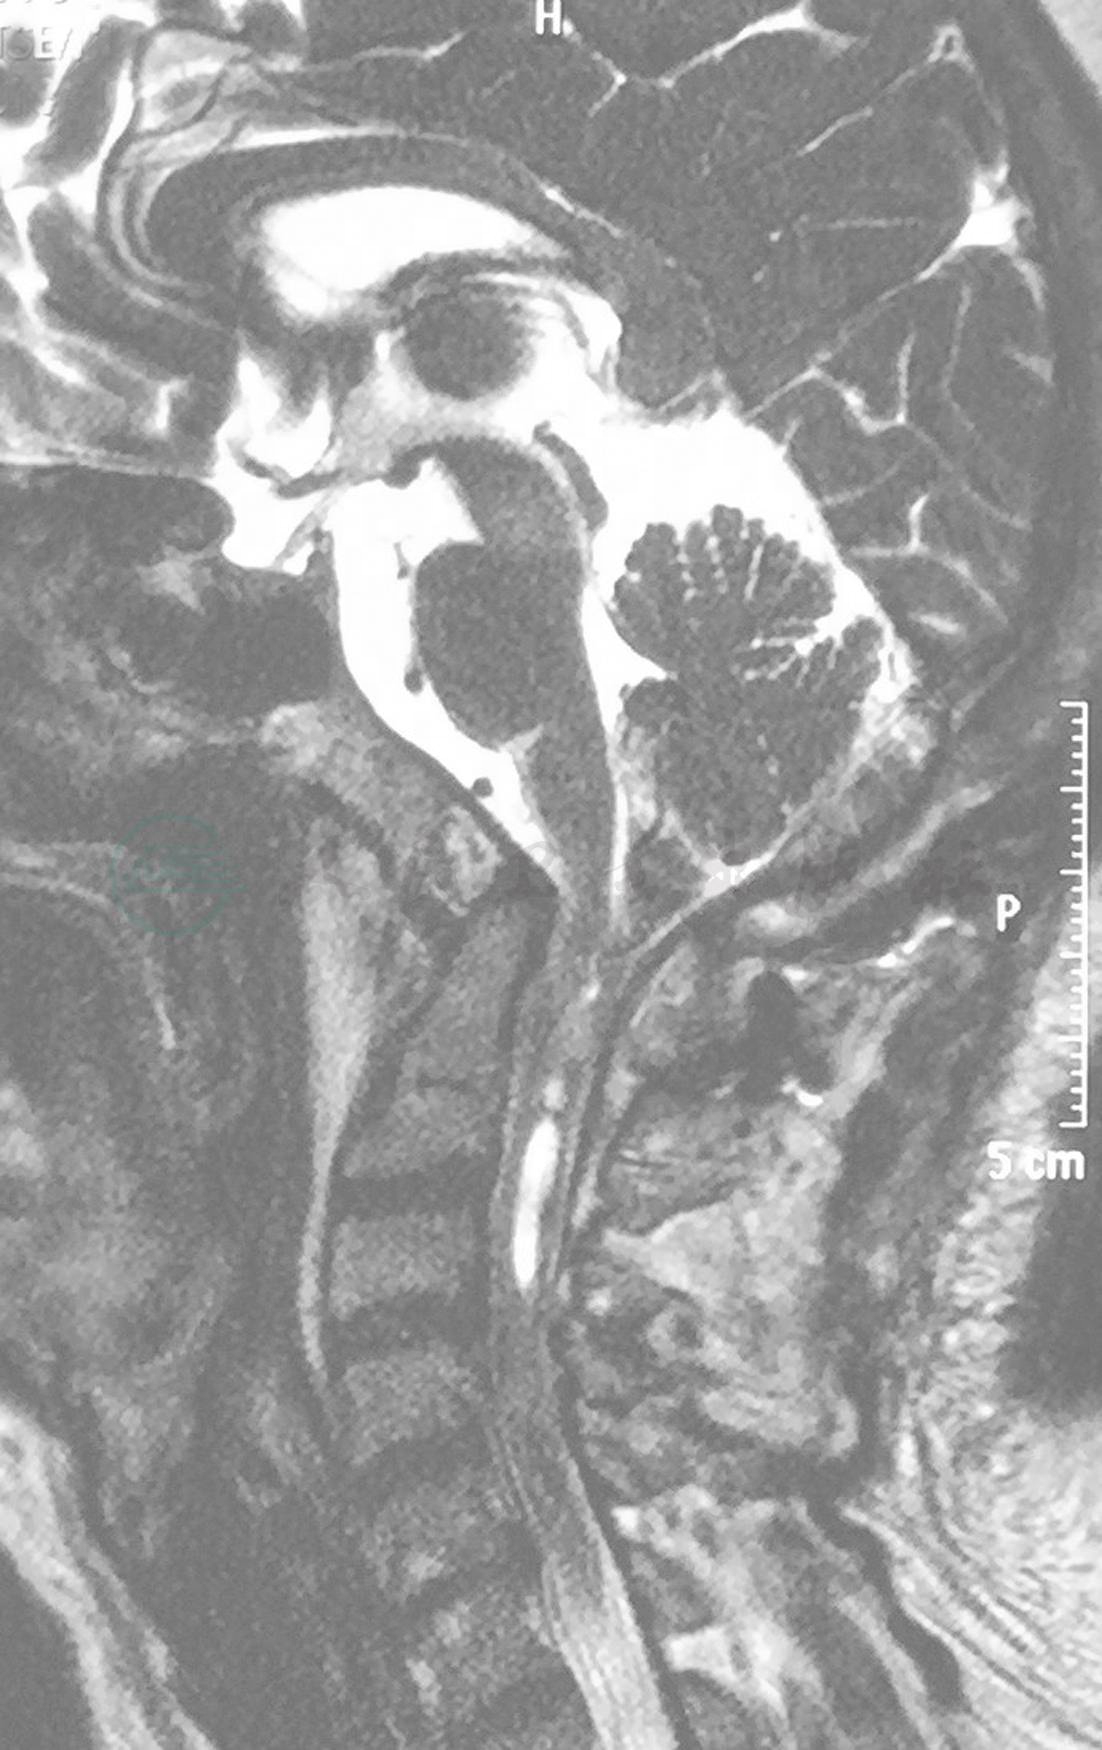

术前磁共振检(MRI)查示:颅底凹陷、寰枕融合畸形,寰齿间距增大,小脑扁桃体下疝合并脊髓空洞(图1)。

图1 术前磁共振(MRI)